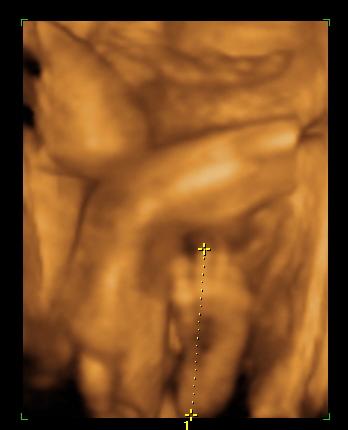

És egy tappancs 2008.03.08 19:45